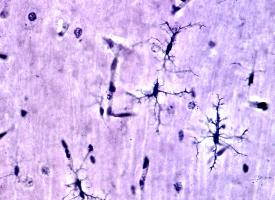

Utiliser l'incidence de certains troubles du sommeil pour prédire la maladie de Parkinson ? Cette vaste étude internationale de l’Université McGill, en identifiant un lien fort entre un trouble du sommeil spécifique, et le développement de la maladie de Parkinson, va en effet contribuer à mieux sélectionner les patients participant aux essais cliniques. Au-delà, cette recherche présentée dans la revue Brain, apporte un facteur prédictif majeur de la progression de la maladie.

Pouvoir sélectionner de « bons » candidats participants pour les essais cliniques : l’étude a suivi 1.280 patients présentant un trouble du comportement du sommeil à mouvements oculaires rapides, caractérisé par des épisodes de rêves violents et une perte de la « paralysie » normale pendant le sommeil. Ces troubles du sommeil paradoxal ont déjà été documentés comme étroitement corrélés à la maladie de Parkinson, la démence à corps de Lewy et à l’atrophie multi-systémique. Pour tester des médicaments susceptibles de réduire les symptômes de la maladie de Parkinson, les chercheurs doivent identifier les personnes à risque élevé mais avant que la maladie ne se développe. La période entre le développement de ce trouble du sommeil paradoxal et les symptômes de la maladie de Parkinson est particulièrement longue, ce qui fait de ces patients de bons candidats pour les essais cliniques visant à tester de nouveaux traitements de « Parkinson ».